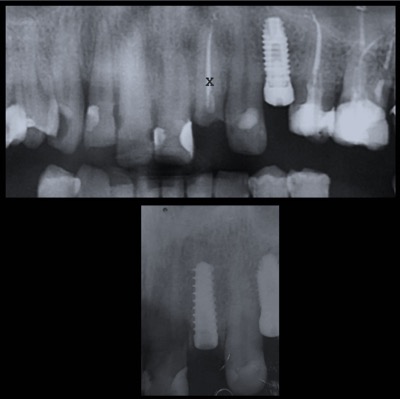

Con l’implantologia oggi è possibile sostituire un solo dente come un’intera arcata anche in casi di deficit ossei grazie alla GBR (rigenerazione ossea guidata) che ci permette di intervenire quando la disponibilità ossea iniziale del paziente non sarebbe sufficiente.

Nulla è per sempre, come anche i denti naturali. Un impianto può andar incontro ad una perimplantite, infiammazione che attacca il tessuto osseo circostante fino a causarne la mobilità. I fattori che predispongono alla perdita di un impianto sono: fumo di sigaretta, scarsa igiene orale, sovraccarico meccanico, predisposizione genetica. Le cause certe non sono ancora del tutto note al giorno d’oggi.

Qualità degli impianti e tipo di trattamento di superficie, caratteristiche nel design della protesi e corretto posizionamento sono fattori fondamentali per ridurre il rischio di perdere un impianto.